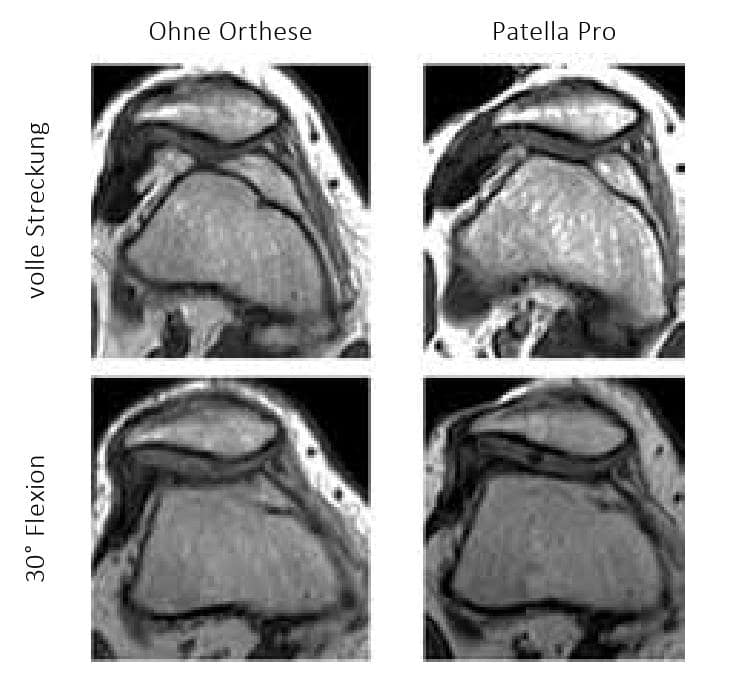

Rezentrierungsorthesen können durch die nach medial auf die Patella wirkende Kraft auch einen direkten biomechanischen Effekt erzielen. So konnte im Rahmen einer Fall-Kontroll-Studie die biomechanische dynamische Wirksamkeit der patellastabilisierenden Orthese „Patella Pro“ (Otto Bock GmbH, Duderstadt; Abb. 1) bei 20 Patienten mit lateraler Patellainstabilität mittels Kernspintomographie (MRT) unter Belastung nachgewiesen werden (Abb. 2). Dabei wurden erkrankungstypische patellofemorale MRT-Parameter im Stehen mit und ohne Orthese bei durchgestrecktem Knie sowie bei kontrollierter Flexion von 15° und 30° untersucht (Abb. 3). Mit angelegter Orthese zeigte sich eine signifikante Verminderung des Patella-Tilt (Abb. 4) und des Bisect-Offset (Maß für die Lateralisierung der Patella; Abb. 5). Der Patella-Tilt verminderte sich um 3.2° ± 2.8° in voller Streckung, um 5.0° ± 3.6° bei 15° Flexion und um 4.0° ± 4.3° bei 30° Flexion. Der Bisect-Offset und damit das Ausmaß der Lateralisierung verminderte sich um 14.2 ± 10.9 % in voller Streckung, um 15.6 ± 12.6 % bei 15° Flexion und um 12.3 ± 11.8 % bei 30° Flexion. Auch die Patellahöhe und der TTTG-Abstand (bei 15° und 30°) waren statistisch signifikant positiv beeinflusst 19.